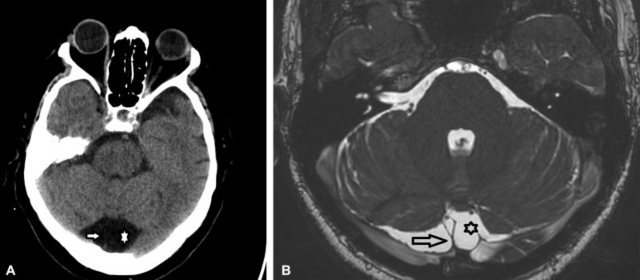

(A-B) TC, corte axial de cerebro (A). Aumento del diámetro de la cisterna Magna (*). Nótese la presencia de estructuras vasculares venosas en su interior (flecha). RM, cortes sagital axial ponderado en T2 (B) se objetiva aumento de los diámetros de la cisterna Magna (*) atravesada por estructuras vasculares (flecha).